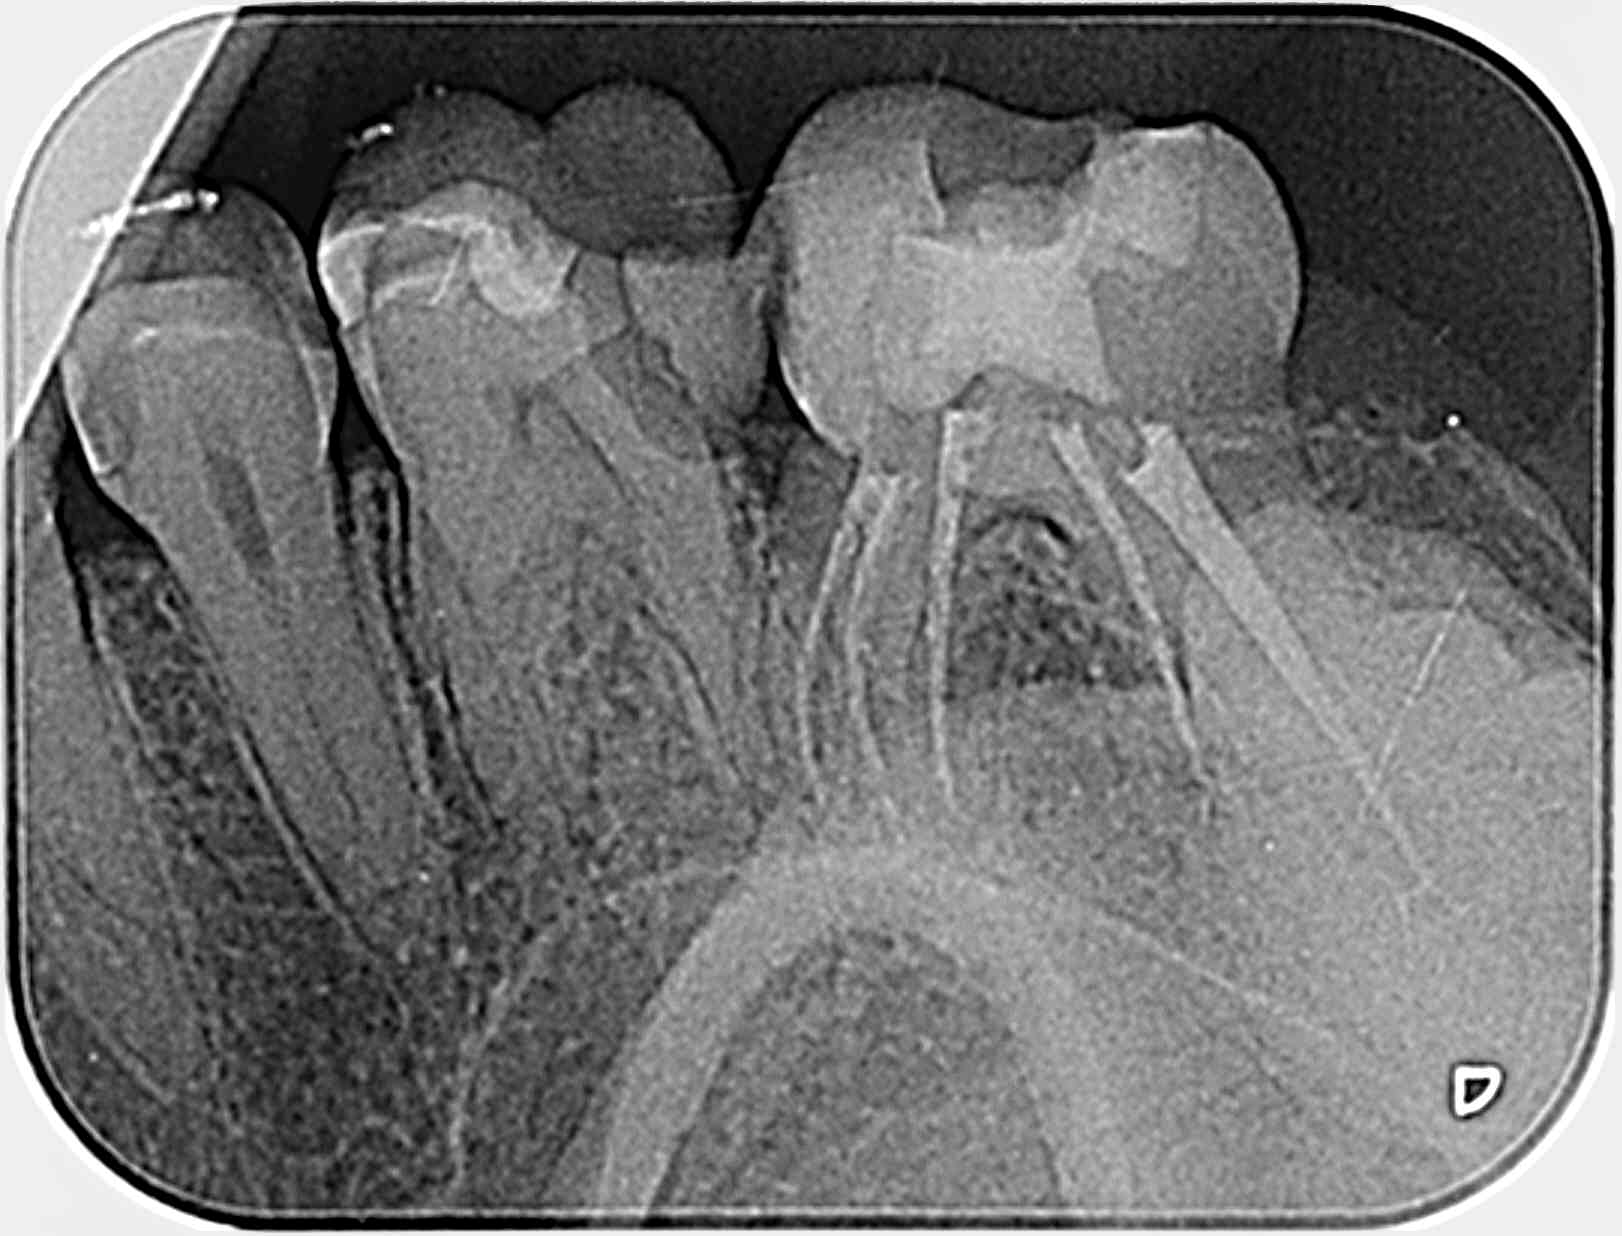

RAC à 0, pour un compo français à 40,97 euros sur une bio mol américaine , 1h30 de travail, sous micro, à 3000 $, avec cavit, pour un patient , ( avec un frère dentiste en Pologne resté sans voix car il facture sa bio 400 euros).